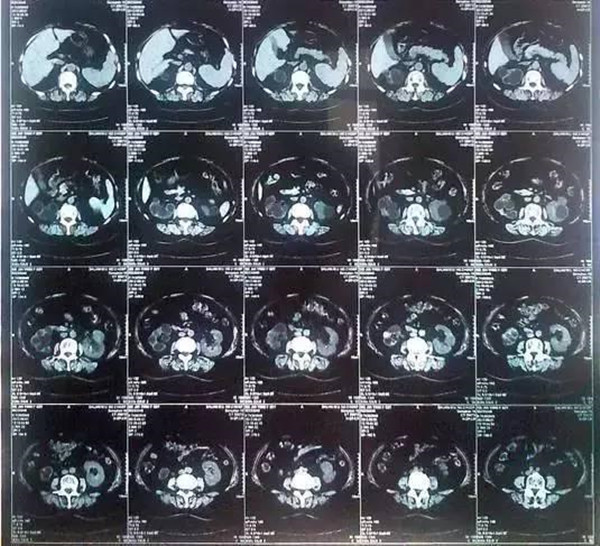

核心提示:55岁的老何是金华东阳市横店镇人,一名普通工人。因为频繁腰疼去医院检查,结果CT显示,他的左肾里竟然密密麻麻布满了石头,几乎把整个肾都塞满了,手术从左肾取出了420颗结石!

55岁的老何是金华东阳市横店镇人,一名普通工人。因为频繁腰疼去医院检查,结果CT显示,他的左肾里竟然密密麻麻布满了石头,几乎把整个肾都塞满了,手术从左肾取出了420颗结石!

医生看了CT的结果显示,非常严肃的告诉他,他的左肾已经被结石占满,必须马上手术治疗。这次手术让主刀医生触目惊心,他们居然从老何的左肾取出了420颗结石。这是他们手术生涯上从来没有遇到过的病例。